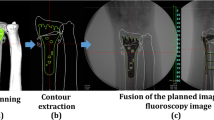

Regarding image fusion, 3D images of preoperative plans were converted to digitally reconstructed radiographs. Bone and implant contour extraction images were created for anterior–posterior and lateral views based on 3D images. Fusion images were displayed on a monitor overlapping the outline of the 3D preoperative plan and the fluoroscopic image. Corrective osteotomy was performed under general anesthesia. In the image fusion group, the outline of the planned image was displayed on a monitor overlapping the fluoroscopy image during surgery. Before starting surgery, the contour extraction image size was calibrated by measuring a known length. A surgeon performed corrective osteotomy based on the fusion image. Before osteotomy, a plate placement image was displayed on the monitor (Fig. 5). In the first step, the plate was placed on the distal radius according to the outline of the plate image and fixed with two temporary fixing wires. Outlines of the anterior–posterior and lateral views were used. According to the direction of the fluoroscopic image, the direction of the contour image was changed to the anterior–posterior or lateral view. Plate placement was checked with a fusion image for each direction. After determining the plate position at the distal radius, distal screw holes were pre-drilled. The plate was then removed leaving the temporary fixing wires. In the second step, osteotomy was performed at a level that did not interfere with the distal screws of the plate. In the third step, the plate was returned to the originally selected position under the guide of the temporary fixing wires, and the distal screws were inserted into the pre-drilled holes. Finally, the distal fragment was repositioned by adapting the proximal side of the volar locking plate to the radius shaft, and the plate was fixed with screws (Fig. 6).

Fusion image of the preoperative plan and fluoroscopy for plate placement. Based on the plate placement image, a contour extraction image was created and displayed on the fluoroscopy image for surgery. The plate was placed to fit the contour line. a Anterior–posterior view, b lateral view. * shows temporary fixing wires